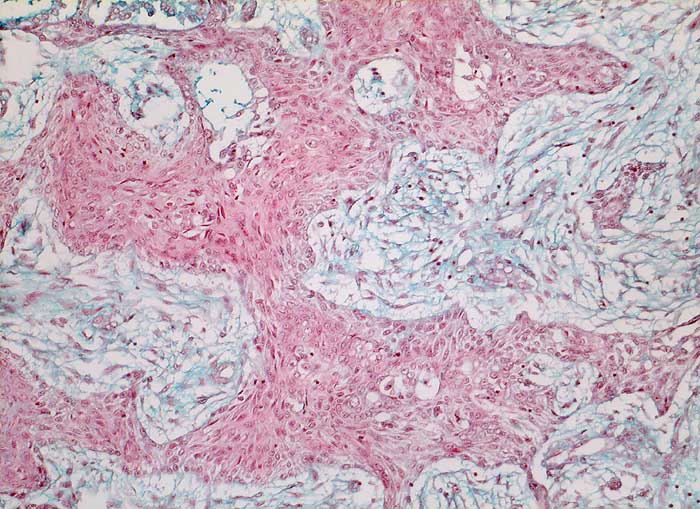

PathoPic ID 5765 - mässig differenziertes Plattenepithelkarzinom

mässig differenziertes Plattenepithelkarzinom

maligner Tumor

Lunge

Solider Tumorzellverband ohne erkennbare Verhornung. Reichlich desmoplastisches Stroma.

Histologie

100